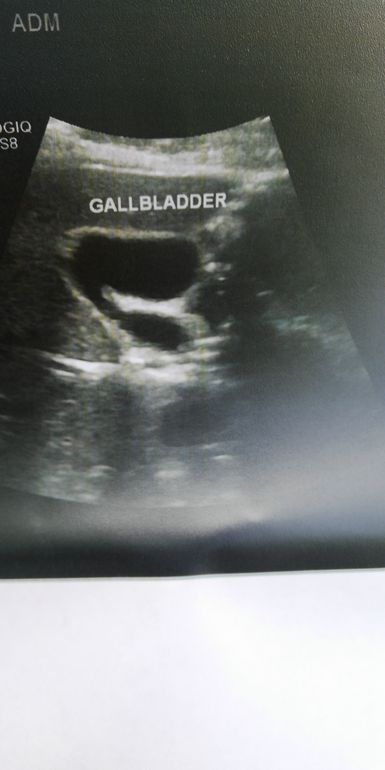

Baby, здравствуйте, это был не желудок, это желчный, были камни,я вовремя обратилась к врачу и сделала узи, были камни до 5мм и их мне удалось растворить слава богу, иначе операция, очень болючие были приступы, сейчас живу обычной жизнью, ем все что хочу, камней нет, единственное осень весна пропиваю по месяцу хофитол по 1 таблетки в день. Так что сходите обязательно на УЗИ желчного, не запускайте, если это камни вполне вероятно что их можно ещё растворить! Если что пишите)

Ох как это похоже на желчный((

Я тоже была уверенна, что желудок. Так же отдавало в спину. Приступы, что вздохнуть нельзя. Сходите на УЗИ.

Была на УЗИ, вы были правы, загиб желчного пузыря, нужно теперь идти к гастроэнтерологу